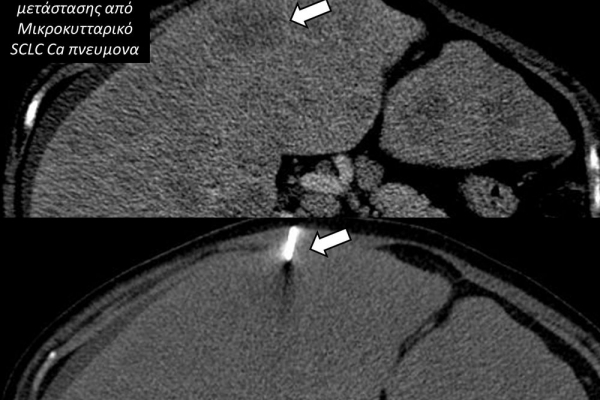

Η διαδερμική βιοψία είναι μία ελάχιστα επεμβατική μέθοδος λήψης υλικού από τον όγκο για κυτταρολογική και ιστολογική εξέταση, από εστιακές αλλοιώσεις του ήπατος, πνεύμονα, νεφρού κλπ. Συστήνεται από τον κλινικό ιατρό ανάλογα με το είδος και το μέγεθος της βλάβης και πραγματοποιείται με ασφάλεια από επεμβατικό ακτινολόγο με την καθοδήγηση αξονικού τομογράφου ή υπερήχων. Στη σύγχρονη ογκολογική θεραπεία όπου γίνεται προσπάθεια καταπολέμησης του καρκίνου σε μοριακό επίπεδο κρίνεται αναγκαία η ακριβής ιστολογική ταυτοποίηση του όγκου ώστε να εφαρμοσθεί εξατομικευμένη θεραπεία για το βέλτιστο αποτέλεσμα. Οι κατευθυνόμενες βιοψίες στοχευουν στο να παρέχουν στον κλινικό ογκολόγο το απαραίτο ιστοπαθολογικό υλικό που θα του επιτρέψει να εφαρμόσει την κατάλληλη θεραπεία για τον ογκολογικό ασθενή.